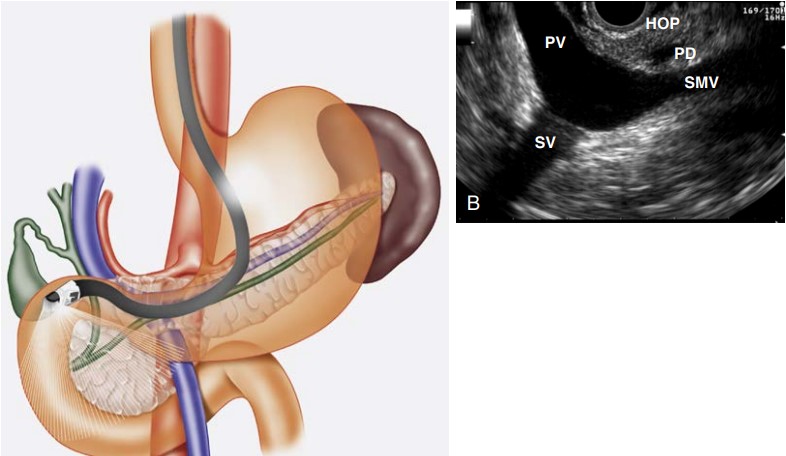

Endoscopic Ultrasonography (EUS) stands at the forefront of diagnosing and managing diseases related to the pancreas, bile duct, and liver. This minimally invasive technique offers a detailed, up-close view of these internal structures, providing invaluable information beyond the reach of traditional imaging methods.

EUS is particularly significant in evaluating pancreatic diseases. Whether it’s identifying benign cysts or assessing pancreatic tumors, EUS’s high-resolution images enable detailed examination, aiding in:

- Diagnosis of Pancreatic Cancers: Early detection is critical, and EUS is often the best tool for identifying small tumors.

- Evaluation of Pancreatic Cysts: Determining the nature of cysts, whether they’re benign or have malignant potential.